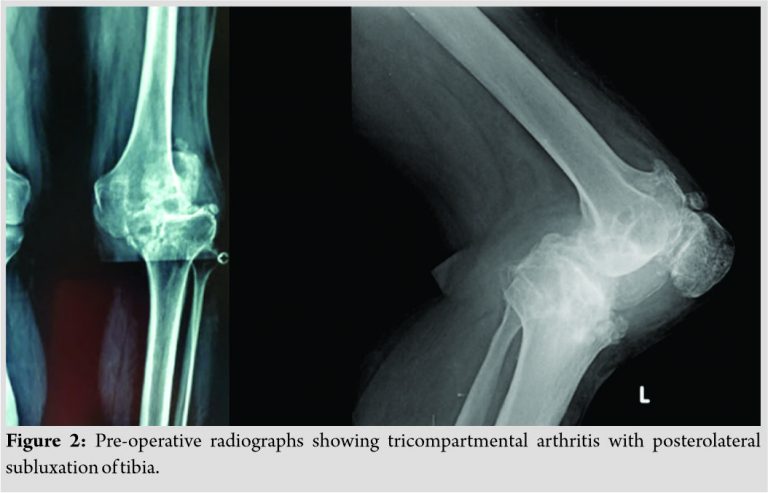

The patient was limping with knee pain when he presented to us. He complained of instability while climbing stairs and walking briskly. Visible deformity of the knee was evident (Fig. 1). The patient was able to extend his knee completely without extensor lag. However, flexion was restricted to 80°. Radiographs revealed severe arthritis with marked posterolateral tibial subluxation (Fig. 2). Pre-operative Oxford Knee Score was 17. Skin condition around the knee was good barring the scar from previous surgeries. Doppler study showed a triphasic flow in distal arteries. The patient had ankle dorsiflexion and plantar flexion of Medical Research Council power 5/5 with intact distal sensations.